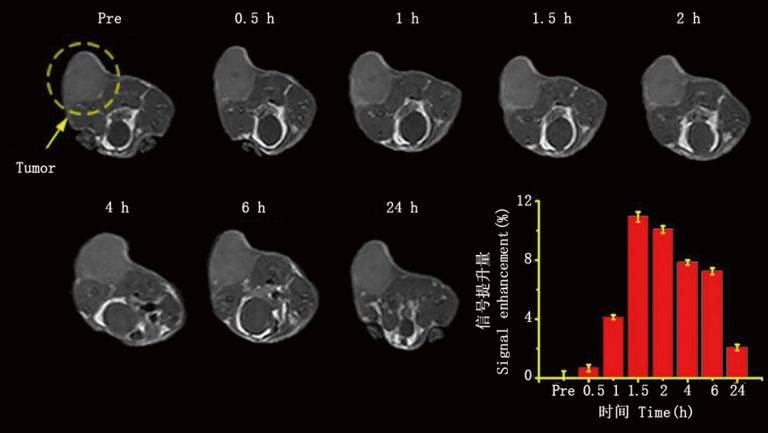

紐邁緊湊型小動(dòng)物磁共振成像系統(tǒng)是一種高效的成像工具,可以快速地提供大鼠和小鼠的活體圖像。相較于傳統(tǒng)的解剖學(xué)方法,活體MRI無(wú)需對(duì)動(dòng)物進(jìn)行任何創(chuàng)傷性操作,從而避免了二次傷害對(duì)實(shí)驗(yàn)結(jié)果的影響。通過(guò)對(duì)同一動(dòng)物進(jìn)行多次成像,我們可以獲得更加精確的疾病進(jìn)展和消退過(guò)程、形態(tài)學(xué)以及定量信息,為研究人員提供了非常有價(jià)值的數(shù)據(jù)。此外,該系統(tǒng)還可以在短時(shí)間內(nèi)完成成像,大大提高了實(shí)驗(yàn)效率和產(chǎn)出。因此,紐邁緊湊型小動(dòng)物磁共振成像系統(tǒng)成為了生命科學(xué)領(lǐng)域中不可或缺的重要工具之一。未來(lái)隨著技術(shù)的不斷升級(jí),這一系統(tǒng)將會(huì)越來(lái)越受到科研人員的青睞,并為我們帶來(lái)更多的收獲和發(fā)現(xiàn)。